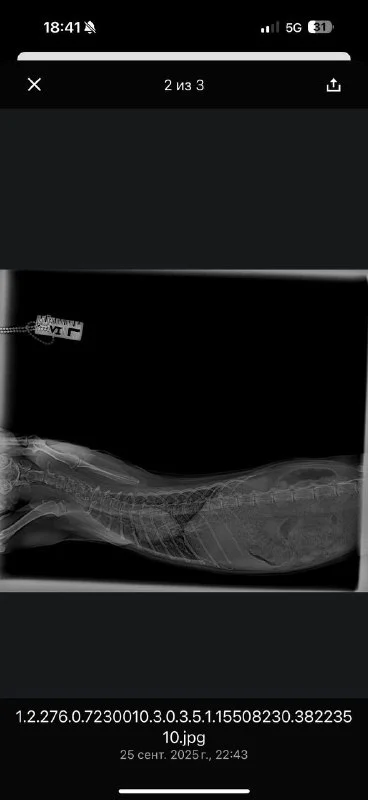

Вчера я ее забрала домой, операция прошла успешно, она уже пытается вставать на все 4 лапы, но у нее действительно есть проблемы с головой, непонятно что со зрением и двигается она только вокруг своей оси, ну ладно с этим потом буду разбираться. Публикую наконец фото рентгена, новый счет (который финально оказался меньше!) ресит с указанием оплаты и баланса.

Рентген ужас,руки в кадре, укладка жуть

Рентген это тот что в имерженси делали это мои руки 🤦🏼♀️ у них бардак конечно, хорошие люди, Михалис хороший хирург, но всегда толпа народа все носятся, но я к ним продолжаю ходить они меня знают и живу рядом